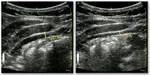

A Deep Learning Localization Method for Measuring Abdominal Muscle Dimensions in Ultrasound Images

Health professionals extensively use Two-Dimensional (2D) Ultrasound (US) videos and images to visualize and measure internal organs …